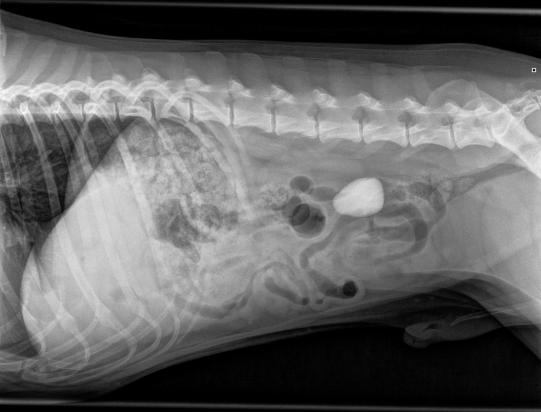

In der Praxis erscheint der Rüde sehr vital und aufgestellt. Beim Abtasten des Bauches ist aber ein harter Knoten zu spüren, welcher den Verdacht nährt, dass sich im Darm des Hundes ein weiterer Stein befindet. Im Röntgen ist denn auch ein dreieckiger, abgerundeter Stein von ca 4x3x2 cm Grösse zu sehen.

Aufgrund des Röntgens ist nicht zweifelsfrei zu klären, ob sich der gefundene Stein im Dünn- oder Dickdarm befindet. Sollte sich der Fremdkörper im Dünndarm aufhalten, muss davon ausgegangen werden, dass er das Darmrohr blockiert und damit eine Operation notwendig ist. Falls sich der Kiesel aber trotz seiner beträchtlichen Grösse schon durch den Dünndarm gezwängt hat und im Dickdarm liegt, kann davon ausgegangen werden, dass er ohne Chirurgie durch den Hund ausgeschieden werden kann.

Ein Ultraschall nährt die Hoffnung, dass letztere Möglichkeit zutrifft. Zur zweifelsfreien Bestätigung wird ein sogenanntes Kontrast-Enema durchgeführt: Hierbei wir durch einen dünnen Katheter ein flüssiges Kontrastmittel in den Enddarm des Hundes eingebracht, welches dann beweist, dass der Stein eindeutig im Dickdarm liegt. Tierarzt und Tierheimpersonal können aufatmen, eine Chirurgie ist nicht notwendig.